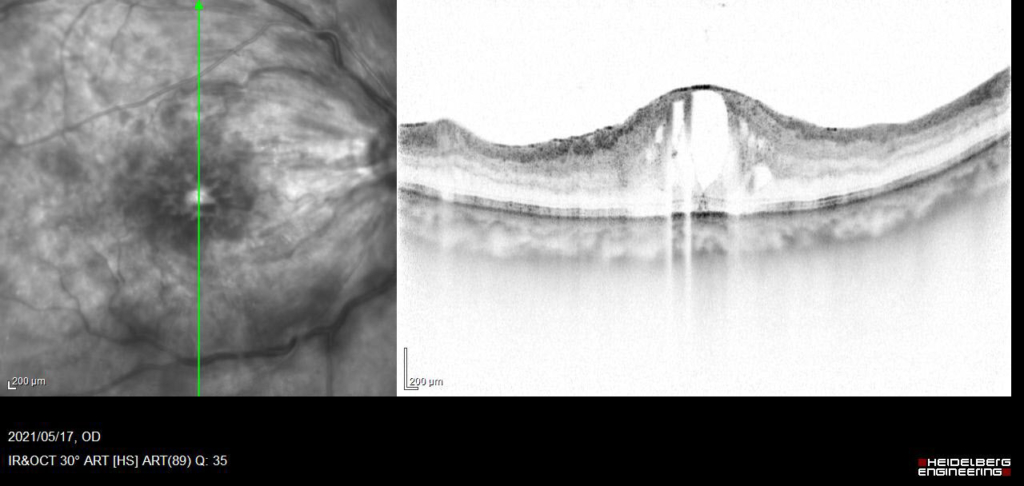

70歳 女性

視力 右眼 0.15(0.3p×+0.25=c-0.75A40°)

主訴 右眼 徐々にかすむ

既往歴 30年前からの糖尿病(HbA1c:7.4)

受診直後より抗VGEF(ラニビズマブ)の硝子体注射を4wおきに施行。

視神経乳頭中心に放射状に静脈に沿って火炎状・線状出血が網膜全体にみられる。